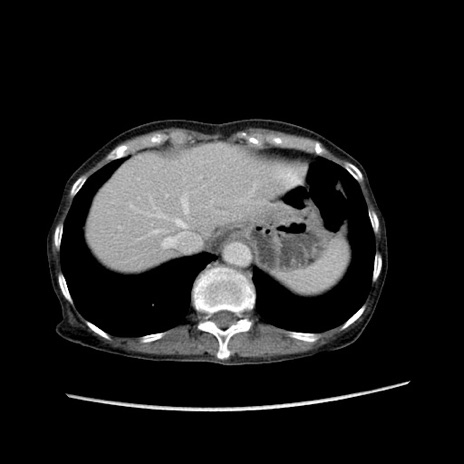

症例25(横断像)

【症例】80歳代女性

【主訴】胸のつかえ感

【現病歴】約9時間前に食後から胸のつかえた感じあり、嘔吐あり、来院。

【既往歴】胃癌(全摘)、胆摘、虫垂炎

【身体所見】心窩部に圧痛あり、反跳痛なし。

【データ】WBC 5700、CRP 0.05